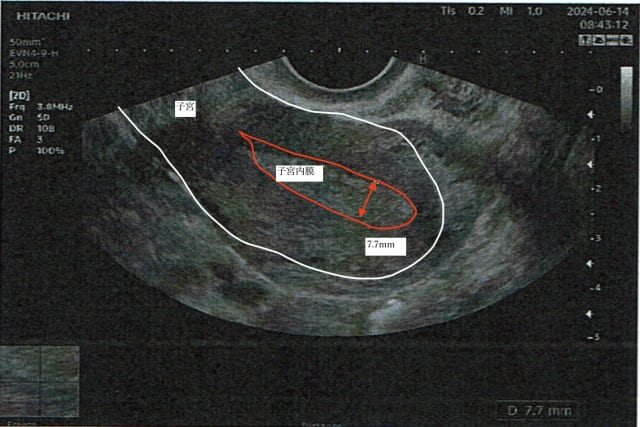

当院の施術で内膜が厚くなる様子

内膜7.7mm

内膜9.8mm(直営よもぎ蒸し併用)当院の施術で良好胚を取得した記録